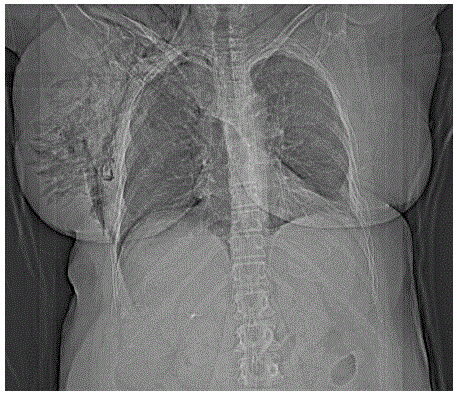

Mulher de 64 anos, vítima de atropelamento, dá entrada no serviço de emergência transportada pela equipe de resgate. Refere dor torácica do lado direito. Apresenta frequência respiratória: 25 ipm, Sat. O2: 90%; frequência cardíaca: 120 bpm; pressão arterial: 140x90 mmHg; Glasgow coma escore: 15. Ao exame clínico murmúrio vesicular diminuído do lado direito, mama direita 3x o tamanho da mama esquerda, enfisema de subcutâneo no hemitórax direito. O raio-X de tórax mostra: